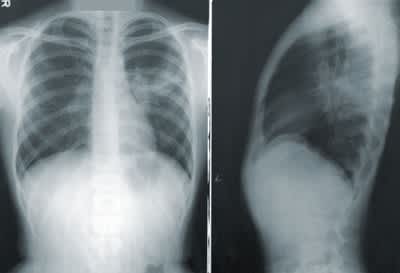

ニューモシツチス肺炎は、ニューモシスチス・イロベチイと言う真菌感染によって発症する肺炎で、発見者の名を取りカリニ肺炎とも呼ばれています。

エイズのように、免疫力の低下した人に合併症として起こる肺炎で、常在菌のニューモシツチスの増殖によって血液中に酸素が取り込めなくなり、低酸素血症を起こします。

リンパ性間質性肺炎は、成熟したリンパ球が肺胞内に溜まる病気で、呼吸困難を起こします。

また、リンパ球が肥大したものを肺リンパ化形成と言います。

このようにHIV感染した場合、最終的な死亡原因が肺炎による事は非常に多くなっています。

また、通常健康な大人で健全な免疫を保持している場合に、1年に2回以上肺炎になることは稀です。

エイズが発症し、免疫が低下することによって反復性肺炎と言って、頻繁に肺炎を引き起こすようになるのです。